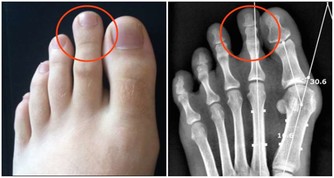

臨床研究發現,人體隨著年齡的增長骨骼中的鈣會隨著流失,從而導致骨質疏鬆等病症,骨質疏鬆為例,50歲以上的發病率為28%,60歲以上的發病率為58%,80歲以上的發病率會高達100%,除了年齡增長必然的鈣質流失外,生活中還有一些飲食上的因素會偷偷的帶走身體中的鈣。所以臨床中有很多案例,吃了將近一年的多的鈣片後去體檢反而骨密度降低了,其實這種情況很有可能是出在了飲食上。那麼究竟是哪些食物能帶走鈣呢?

菠菜中含有大量的草酸,與血液中的鈣結合便會行成沉澱物草酸鈣,這樣血液中的鈣含量會大幅降低,最終導致骨鈣的含量降低。沉澱物草酸鈣屬於不溶物,只能隨著血液到腎臟代謝到體外,如果排泄出了問題,還會有形成結石的可能性。

日常生活中不光菠菜中含有草酸,莧菜中的草酸含量也很高,每一百克的莧菜中就有1142mg的草酸,每一百克的菠菜中有606mg的草酸。還有油菜、小白菜、韭菜、蒜苗、茭白、筍、柿子椒中都不同含量的草酸。吃之前可先進行焯水處理,或吃後大量飲水,促進排尿,利於沉澱物排出體外。日常中要注重食材的搭配,每餐最好不要選擇過多的含草酸的食物,應搭配一些草酸含量低的食物,例如瓜類,冬瓜、南瓜、黃瓜,還有菜花類的食物。